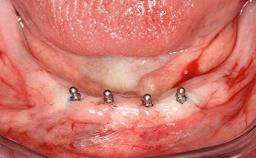

Surgical treatment of a 67-year-old male patient exhibiting an extended edentulous space in the anterior maxilla after the removal of three hopeless incisor teeth.

The video demonstrates implant placement using a surgical stent according to the principle of prosthodontically driven implant placement. The deficient ridge is augmented with locally harvested autologous bone chips, a superficial layer of xenogenic DBBM particles and a resorbable collagen membrane. The surgery is completed with a precise, tension-free primary wound closure.

# of Teeth 4

# of Implants 2

Bone Augmentation Horizontal|Simultaneous

Augmentation Materials Autogenous chips|Xenogenous|Membrane

Bone Volume Deficient horizontally, allowing simultaneous augumentation